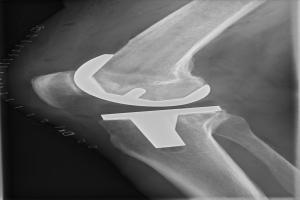

Schüler entdecken spannende Berufsfelder von Pflege bis Chirurgie im Krefelder Krankenhaus

Von Ultraschall-Untersuchungen bis zum Hightech-Lager: Wie ein Krankenhausbesuch Jugendlichen die Vielfalt medizinischer Berufe zeigt. Ein Tag voller Aha-Momente und neuer Perspektiven.